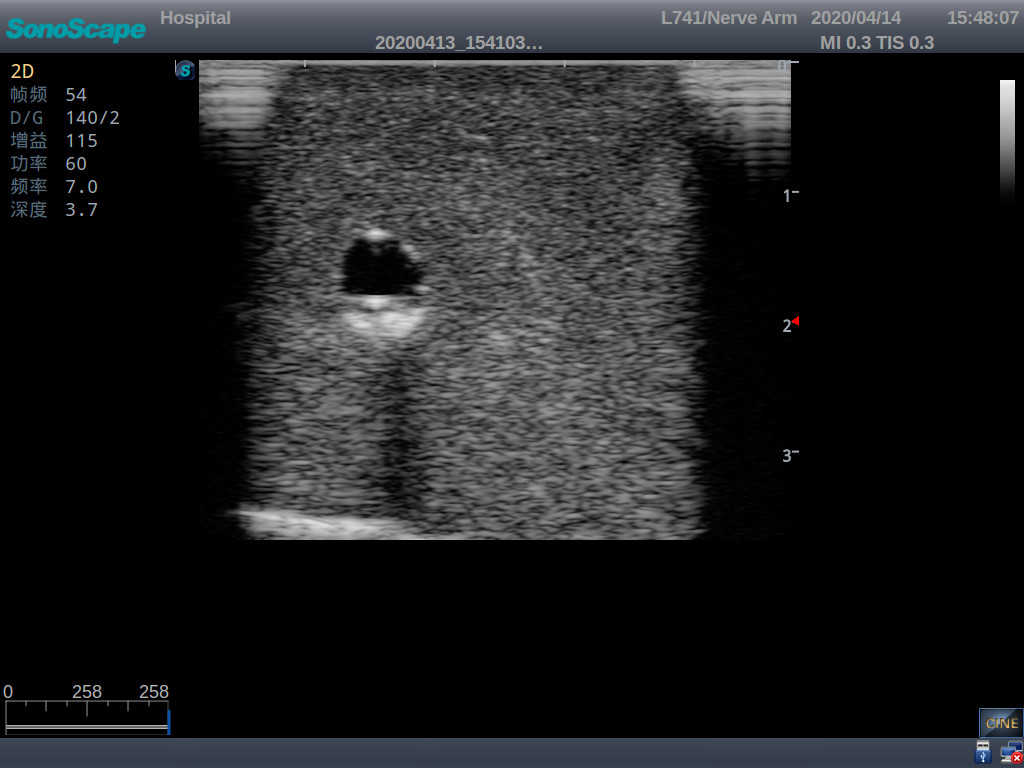

2)   It can be used by real ultrasound machines

3)   Clear and real images of the tissues and organs (basilic vein and superior vena cava)

4)   When conducting vascular puncture, the piercing can be truly felt, and venous blood outflow can be seen

5)   Observe the guide wire marches

6)   Detect whether the catheter is properly placed